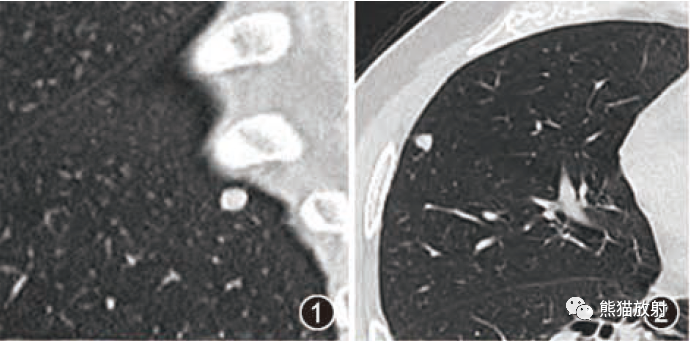

肺转移瘤的十种不典型CT表现  肺内淋巴结的CT表现特点及与病理对照

肺内淋巴结的CT表现特点及与病理对照  肺实变与肺不张的CT鉴别诊断